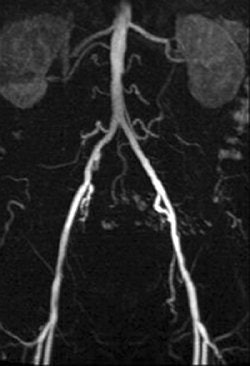

Of the nine patients, the majority had arterial occlusive disease of the iliac axis. The patients underwent angiography and angioplasty with a 6-French introducer left in the common femoral artery.

For the patients, maximum intensity projections (MIPs) were calculated from the contrast-enhanced images. Image quality for evaluating the renal arteries was graded on four-point scale (1 = excellent, 4 = poor). In the phantom, intraluminal signal intensity was measured distal to the tip of the catheter along the tube.

| A 78-year-old man with peripheral arterial occlusive disease. Lumbar arteries are evident with both MRI acquisition techniques. Iliac axis has good runoff on both sides after percutaneous transluminal angioplasty (above). Anteroposterior maximum intensity projection 3D fast low-angle shot (FLASH) intra-arterial MR aortogram obtained with standard technique (below). |

According to the results of the patient study, both techniques were well tolerated and had no side effects. In addition, the diagnostic value of GRAPPA MRA was given an average grade of 2.2 compared to 2.0 for FLASH MRA. Using the parallel acquisition technique, the CNR ranged from 32.0 in the renal arteries to 125.5 in the aorta.